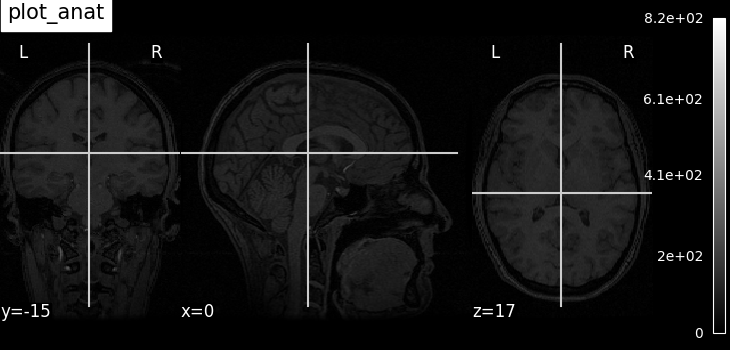

plot_anat

Plotting an anatomical image